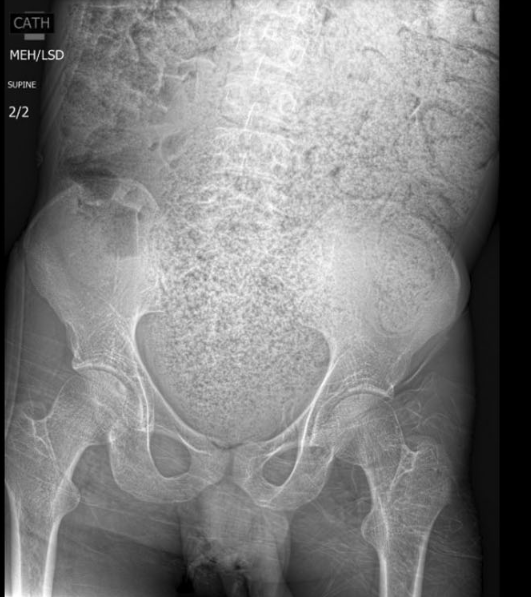

M Matar et al. J Pediatr Gastroenterol Nutr. 2026;82:487–494. Chronic nonbacterial osteomyelitis associated with pediatric inflammatory bowel disease: : A multicenter retrospective study from the Paediatric inflammatory bowel disease Porto Group of ESPGHAN

- CNO presented in 15 patients (33%) within 3 months of IBD diagnosis, and in additional 20 (44%) patients after IBD diagnosis; in 10 (22%) patients CNO preceded the diagnosis of IBD with a median time 46 (25–248) weeks

- Complications occurred in six patients and included vertebral collapse, bone fracture, and bone deformity. In eight (18%) subjects vertebral collapse was present already at the time of diagnosis.